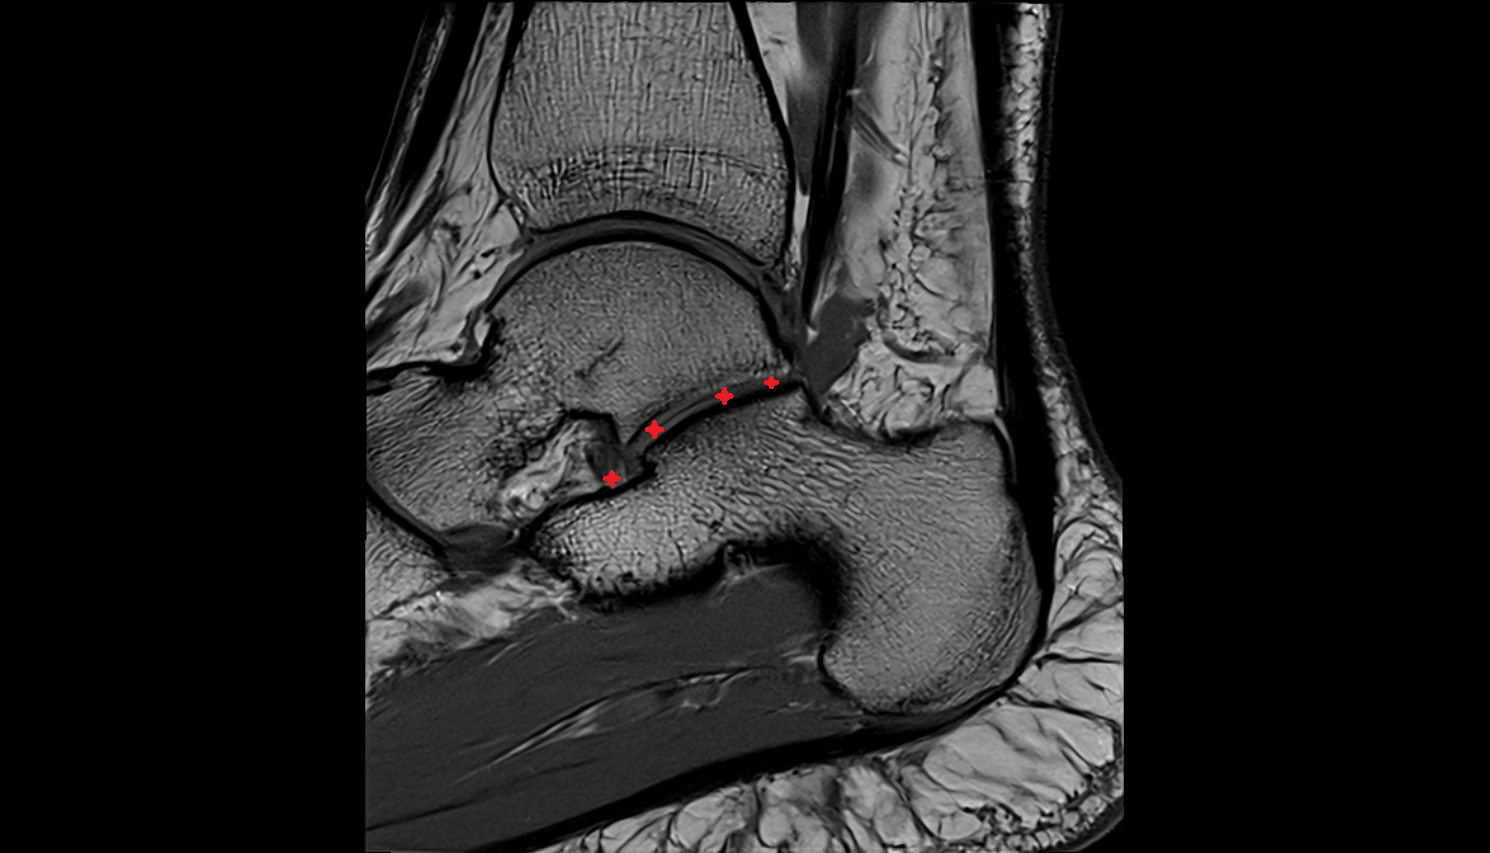

- Talus

- Body of talus

- Neck of talus

- Calcaneus

- Sustentaculum tali

- Ankle joint

- Talocalcaneal joint

- Anterior talofibular ligament

- Posterior talofibular ligament

- Deltoid ligament complex

- Talocalcaneal interosseous ligament